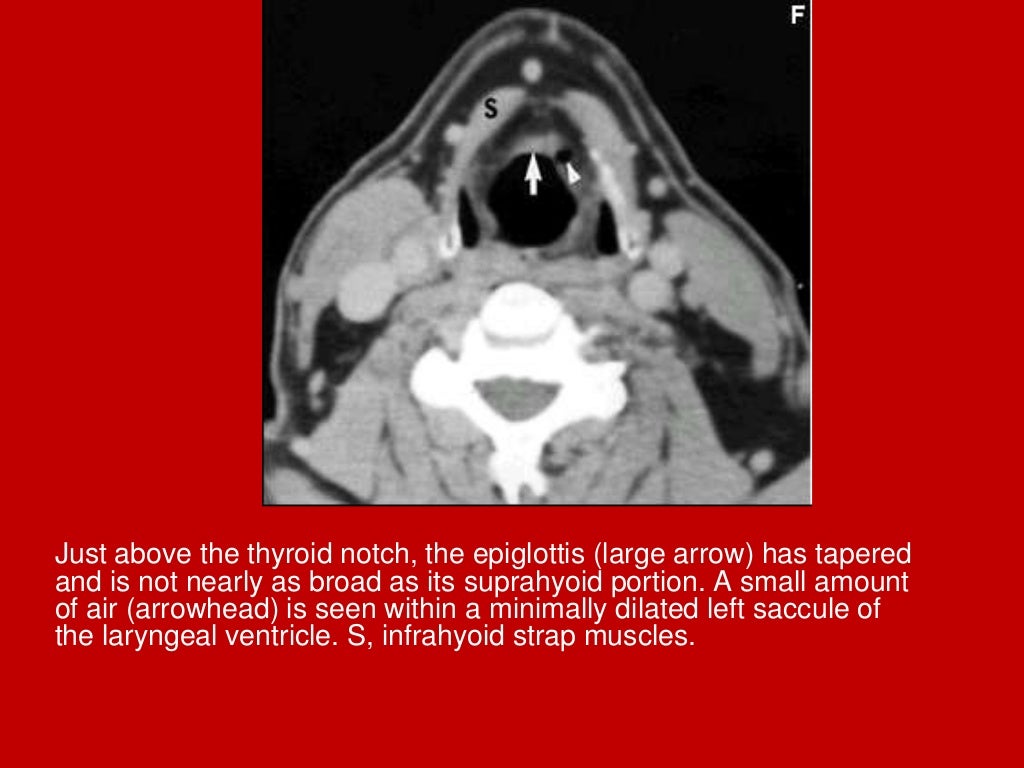

Ct Anatomy Of The Larynx . 21 articles feature images from this case. The purpose of this article is to briefly review currently used imaging protocols, key anatomic structures in the larynx and hypopharynx. The larynx consists of a cartilage skeleton, as well as internal structures that are divided into three subsites, mainly for the purposes of laryngeal cancer. Scrollable ct highlighted the anatomy of the neck. 152 public playlists include this case. Ct is the preferred modality for laryngeal trauma, as it can be performed more simply than mri in the acute or immediate subacute clinical. This article focuses on the use of ct imaging in the evaluation of the larynx, with particular focus on laryngeal neoplasia, trauma,.